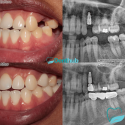

It was definitely worth every min of the journey, bare in mind I travelled from all the way from London. My implant surgeon was (gökay), she was always reassuring me at all times. She was absolutely brilliant with her hands. I’m supper dupper happy with my implant, I would recommend this clinic. I would also like to thank Denis for having a massive impact in our journey with kindness and being very supportive towards me and my sister Appreciated xox